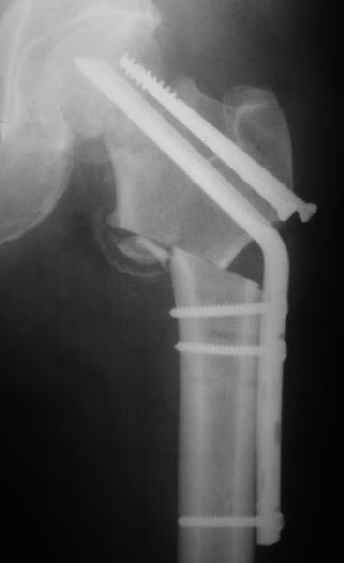

Мужчину 56 лет оперировали у нас в августе 2003 г. - вальгизируюшая остеотомия из-за позднего (через 2 мес. после травмы) поступления с переломом шейки бедра (картинки 1,2). Курильщик, соматической патологии не было. Сейчас поступил с жалобами на проблемы в области тазобедренного сустава, на снимках 3,4 видно вырезывание клинка.Чтоб можно посоветовать в этой ситуации? Заранее спасибо.

A male 56 years old was operated in Aug 2003 - valgus osteotomy performed because of delayed admission with neck fracture (2 months) images 1,2. Smoker, no other major medical problem. Now he re-admitted with the images 3,4.What would you do in the situation?THX in advance.

The osteotomy seems to be showing bony union. (New bone at the medial aspect). There is a big step in the union. The distal fragment is way out laterally.There is overiding of the neck over the head. The screws are out superiorly and the blade also coming out. There is no union of the neck fracture. The head does not seem to be normal- distorted in shape and probably starting of AVN too.

It will be a futile attempt now to get the neck fracture unite. The head has to come out and has to be replaced. Then comes the problem of the malaligned upper shaft. If it has united ( as what I think now) the union has to be undone and fragments aligned before introducing the stem.

If replacement is considered, the osteotomy has to be realigned as mentioned earlier.

Possible reasons why this happened: 1) There is not sufficient purchase of the screws into the head. In fact one can see some threads crossing the fracture site. This will prevent union across. Even the blade probably has less purchase. 2) After the osteotomy the distal fragment will have to be pushed more medially ( as we used to do McMurray's osteotomy 30 years ago) or abducted and fixed so the the fracture line becomes horizontal when the limb is brought to neutral.There is no abduction (so it is not a valgus osteotomy) and in fact the fragment is pulled out laterally. The fracture line has remained vertical and on weight bearing the shearing forces have pulled the implants superiorly. I am waiting for the answer from the replacement specialists.